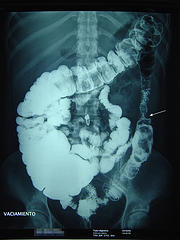

technorati tags: left bowel obstruction, mechanical obstruction, diverticulitis, intestinal obstruction, surgery, acute abdomen, abdominal, medicine, medicina, unbounded medicine